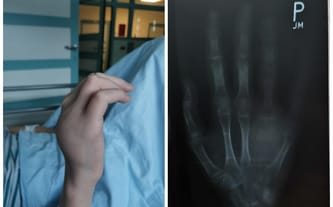

Zaczęło się bardzo niewinnie. Na prawej dłoni Pawła pojawiło się małe wybrzuszenie. Ze względu na to, że syn początkowo nie odczuwał żadnych dolegliwości, zbagatelizował sprawę, myśląc, że guzek sam się wchłonie. Niestety, tak się nie stało. Gdy guz zaczął rosnąć, poinformował nas o nim i natychmiast zgłosiliśmy się do lekarza.

Ortopeda wykonał prześwietlenie dłoni, na którym wyszło, że Pawłowi brakuje kości palca 4. Zlecił także dalszą diagnostykę. Kolejne wyniki okazały się być przerażające — nieoperacyjny guz olbrzymiokomórkowy kości. Szybko rozpoczęliśmy leczenie onkologiczne. Na szczęście, guz okazał się być łagodny. Później otrzymaliśmy kolejną dobrą wiadomość, która napełniła nas wielką nadzieją! Przyjmowana chemia zaczęła działać, guz zmniejszał się i zaczął zwapniać.